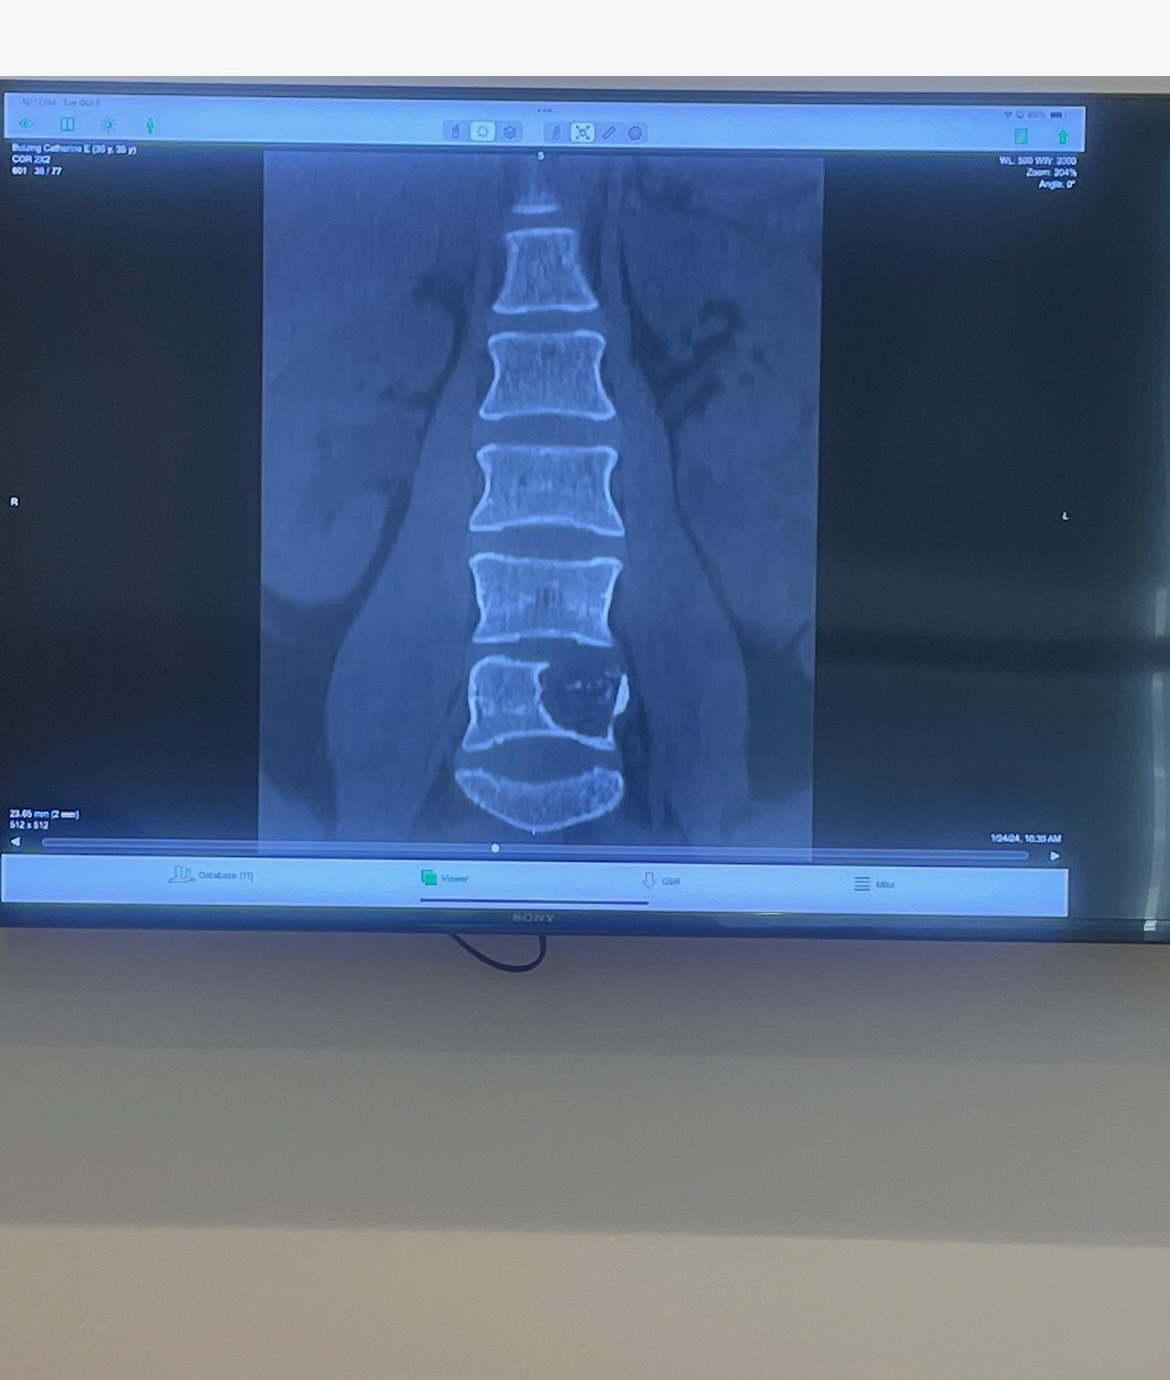

With insurance in place by early 2024, Caela began a long and painful journey of doctor visits, biopsies, injections, and therapies. After nearly a year of searching for answers, she was finally diagnosed with a rare spinal tumor—osteoblastoma—in her L5 vertebra.

In December 2024, Caela underwent two major surgeries to remove the tumor and stabilize her spine with rods and screws. She fought hard through recovery, but in April 2025, the tumor returned—and 4mm of bone is already gone.

Now, she faces a second complex surgery with a team of top specialists, including a world-renowned bone tumor expert. During the operation, doctors will attempt to remove the mass and biopsy for osteosarcoma. There are still many unknowns—possible radiation, additional rods, and months of recovery ahead.